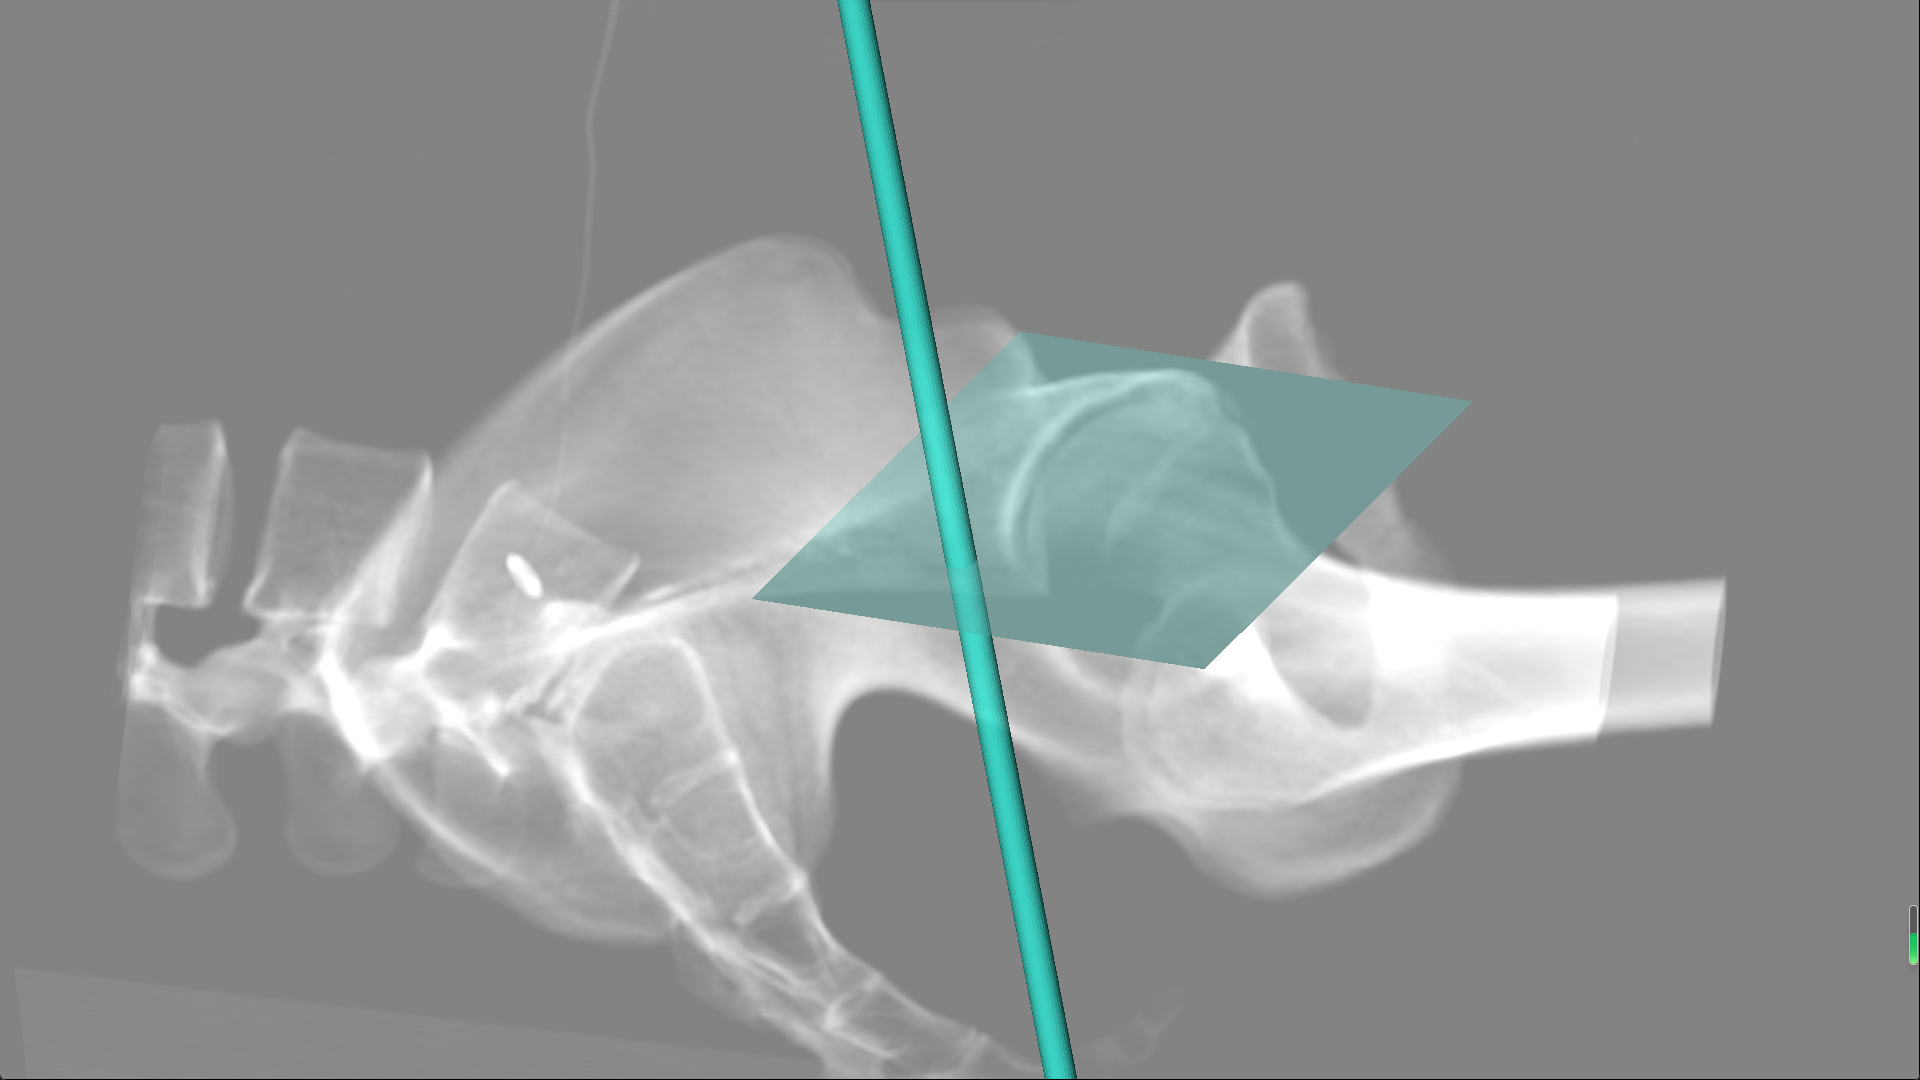

术中的操作图片.png

手术过程中通过混合现实设备观察到的螺钉和骨折位置